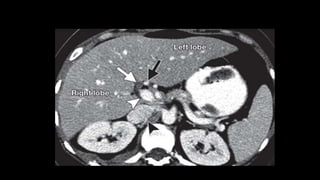

• Liver is divided into a functional

left and right liver by a main

scissurae containing the middle

hepatic vein.

• This is known as Cantlie's line.

• Cantlie's line runs from the

middle of the gallbladder fossa

anteriorly to the inferior vena

cava posteriorly.

• Right hepatic vein divides the

right lobe into anterior and

posterior segments.

• Left hepatic vein divides the left

lobe into left medial and left

lateral sections.

• The portal vein divides the liver

horizontally into upper and lower

segments.